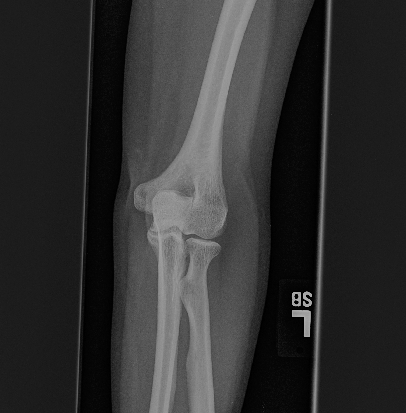

To tackle these problems, we propose to estimate the soft tissue image and bone image simultaneously without losing the linear relationship between image intensity and physical property of the imaging objects. Two examples from our method is shown in Fig. 1. The bone details are enhanced, which is theoretically guaranteed. The details of our method will be explained in later sections.

As shown in the left column of Fig. 1, bones are usually surrounded by the soft tissue. This physical configuration is similar with many natural scenes. One example is the foggy weather, as shown in Fig. 2 (a). The fog can be considered as “soft tissue” (low density) and the buildings can be considered as “bone” (high density).

We performed three experiments for our method. First, we perform our method on several X-ray images, showing our method is not restricted by specific imaging objects. Second, we compared our method with image enhancement method and dehazing method, showing that our modification of the original dehazing indeed helps in this task. Third, we perform our method on a hand X-ray image dataset, showing its effectiveness and efficiency.

Several results from our method are shown in Fig. 7. The left column is the original input image. The right two columns are the soft tissue and bone image, respectively. It can be told that the soft tissue image is smooth as we assumed. Meanwhile, the bone image has better image contrast as desired. Moreover, our method can reach real-time performance on these X-ray images. The running time of our method on these images is reported in Table I.